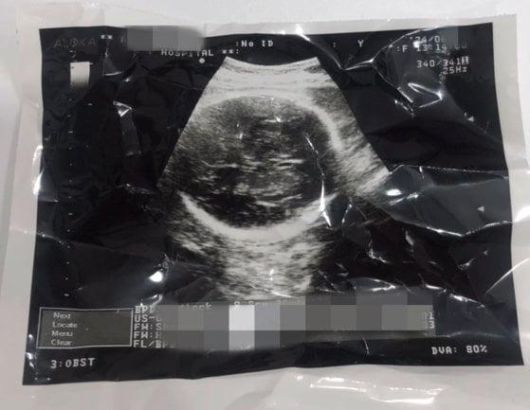

임신 36주 차에 임신중지(낙태) 수술을 받았다고 주장한 한 유튜버가 촬영한 자신의 복부 초음파 사진. 유튜브 캡처 |